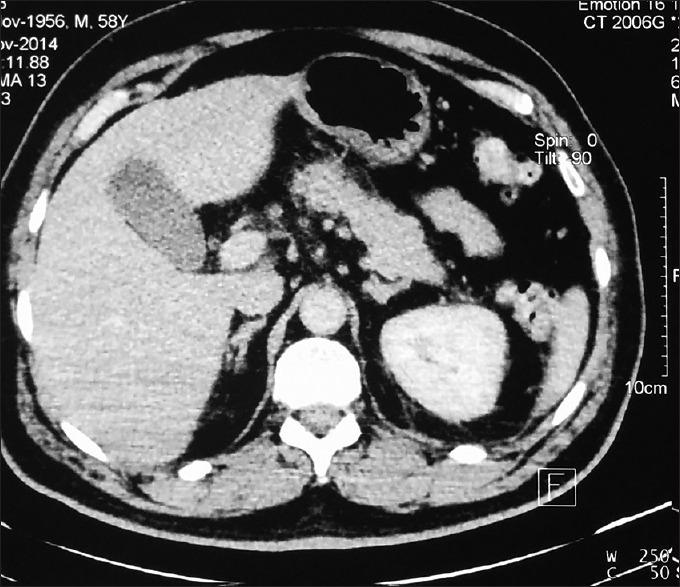

Hypertriglyceridemia (HTG) is the third leading cause of acute pancreatitis (APs) worldwide which is invariably associated with elevated pancreatic enzyme levels. We present a case of HTG-induced recurrent AP with normal serum amylase and lipase levels in a patient of Syndrome Z.

摘要

高甘油三酯血症(HTG)是全球急性胰腺炎(APs)的第三大主要病因,其总是与胰腺酶水平升高相关。我们报告一例Z综合征患者发生HTG诱导的复发性AP,但其血清淀粉酶和脂肪酶水平正常。